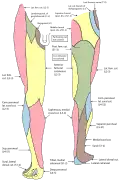

L'artère fémorale.- Nerfs cutanés du membre inférieur droit. Vues de face et de derrière.

Nerfs cutanés du membre inférieur droit. Vues de face et de derrière.

Nerfs cutanés du membre inférieur droit. Vues de face et de derrière. Diagramme de la distribution segmentaire des nerfs cutanés de la plante du pied.